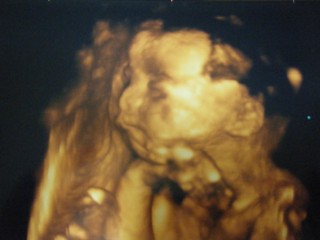

写真:24w1d:ぴぐさん

7ヶ月目に入ってすぐの妊婦健診でした! 体重は572gで少し小さめ。 こっちを向いて手を挙げてる感じ。 まだ性別は分からないから赤ちゃん赤ちゃんって呼んでます。 目の所が目玉があるみたいに見えるけど実際は目をつぶってるらしいですw ちょっとホラーマンっぽくてお気に入りの1枚です(*'▽'*)